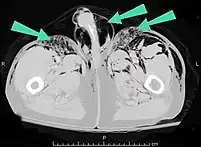

| An abdominal CT scan of a patient with subcutaneous emphysema (arrows) | |

Significant cases of subcutaneous emphysema are easy to diagnose because of the characteristic signs of the condition.[1] In some cases, the signs are subtle, making diagnosis more difficult.[13] Medical imaging is used to diagnose the condition or confirm a diagnosis made using clinical signs. On a chest radiograph, subcutaneous emphysema may be seen as radiolucent striations in the pattern expected from the pectoralis major muscle group. Air in the subcutaneous tissues may interfere with radiography of the chest, potentially obscuring serious conditions such as pneumothorax.[18] It can also reduce the effectiveness of chest ultrasound.[27] On the other hand, since subcutaneous emphysema may become apparent in chest X-rays before a pneumothorax does, its presence may be used to infer that of the latter injury.[13] Subcutaneous emphysema can also be seen in CT scans, with the air pockets appearing as dark areas. CT scanning is so sensitive that it commonly makes it possible to find the exact spot from which air is entering the soft tissues.[13] In 1944, M.T. Macklin and C.C. Macklin published further insights into the pathophysiology of spontaneous Macklin's Syndrome occurring as a result of a severe asthmatic attack.